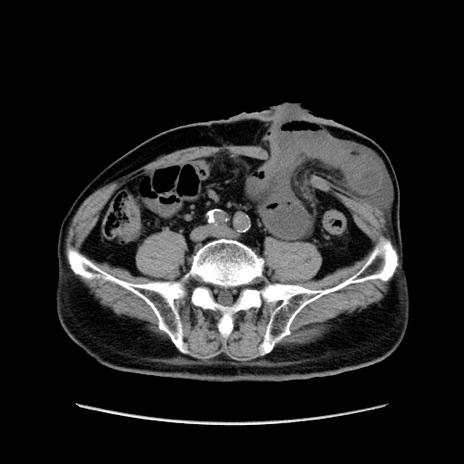

症例24(横断像)

【症例】80歳代男性

【主訴】左側腹部痛、嘔吐

【現病歴】本日早朝より左腹部に痛みあり。昼頃嘔吐認めたため、救急要請。

【既往歴】直腸癌(Mile手術)、胆摘

【身体所見】意識清明、BT 35.9℃、BP 221/93mmHg、SpO2 97%(RA) 、腹部:左ストーマ周囲に限局性の腹部膨隆あり。 膨隆部自発痛・圧痛あり・軟。

【データ】WBC 7700、CRP 0.09